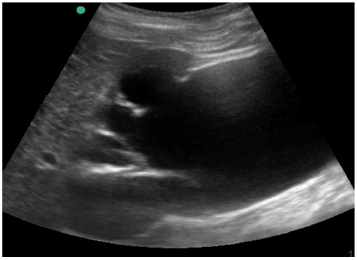

Um paciente de 72 anos de idade foi para a Unidade de Terapia Intensiva (UTI). Institucionalizado, com duas internações nos últimos seis meses por conta de sepse de foco urinário. Na admissão, realizou ultrassonografia abdominal com o achado demonstrado na imagem apresentada. Os exames laboratoriais mostraram ureia = 230, creatina = 10 e potássio = 7,5.

O que tem demonstrado nessa ultrassonografia beira-leito e qual a conduta a ser tomada?